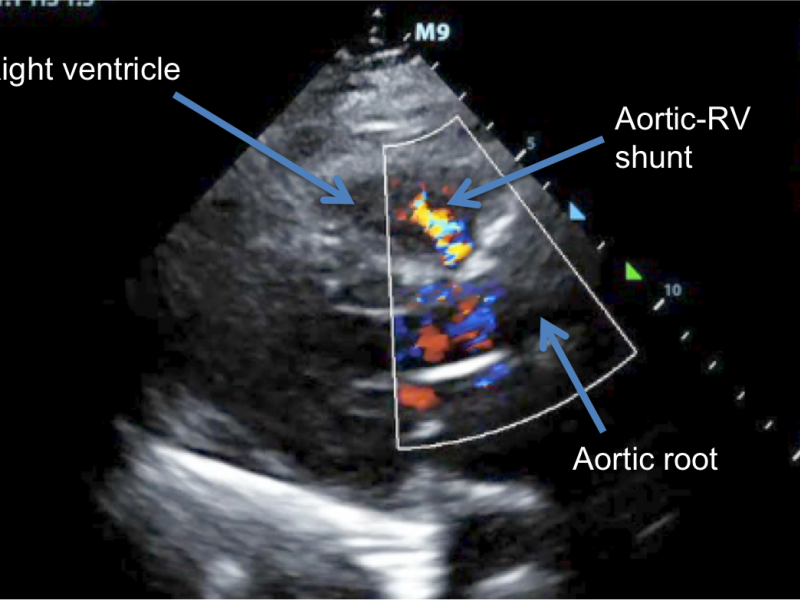

Doppler Echocardiography: Unique post-TAVR Jet

July 12 2017

There's some color that doesn't belong here: The Jet from